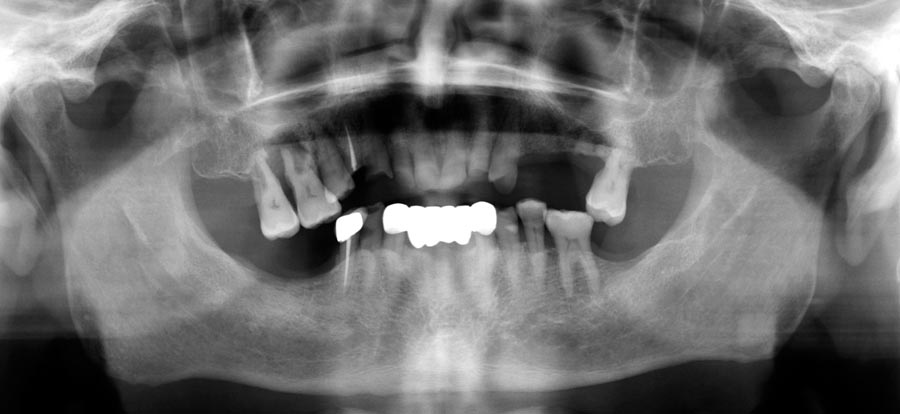

Smile GalleryImplant RestorationsFull Mouth Implant Restoration 1 of 13 Pre-operative smile Pre-operative smile Pre-operative frontal view, lips retracted Pre-operative panoramic image (note bone levels) Post-surgical panoramic image Surgical temporary bridge (note convex contours) Delivery of surgical temporary bridges in both upper and lower Two weeks post-op surgery and temporaries (note amazing tissue response) Three months post- surgery. (Note tissue development) Definitive implant bridges (FP-2) Post-treatment panoramic image Final result smile Final result smile